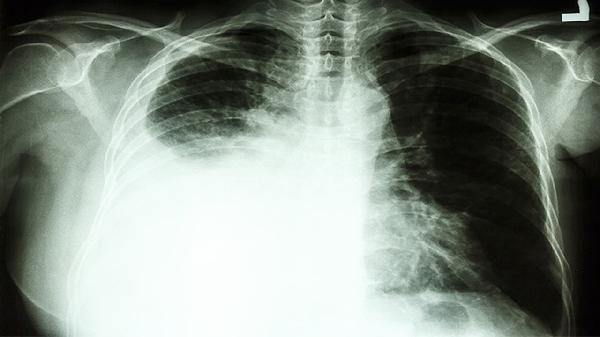

当肺囊肿直径超过5厘米或出现并发症时,手术成为必要选择。囊肿合并感染会引发发热、咳嗽脓痰等症状,需先使用注射用头孢呋辛钠等抗生素控制感染后再手术。囊肿压迫支气管可能导致呼吸困难,囊肿破裂会引起气胸或咯血,这些情况需紧急行胸腔镜下肺囊肿切除术。先天性多发性肺囊肿若影响肺功能,可能需进行肺叶切除。术后需预防性使用盐酸左氧氟沙星片防止感染,并定期复查肺功能。